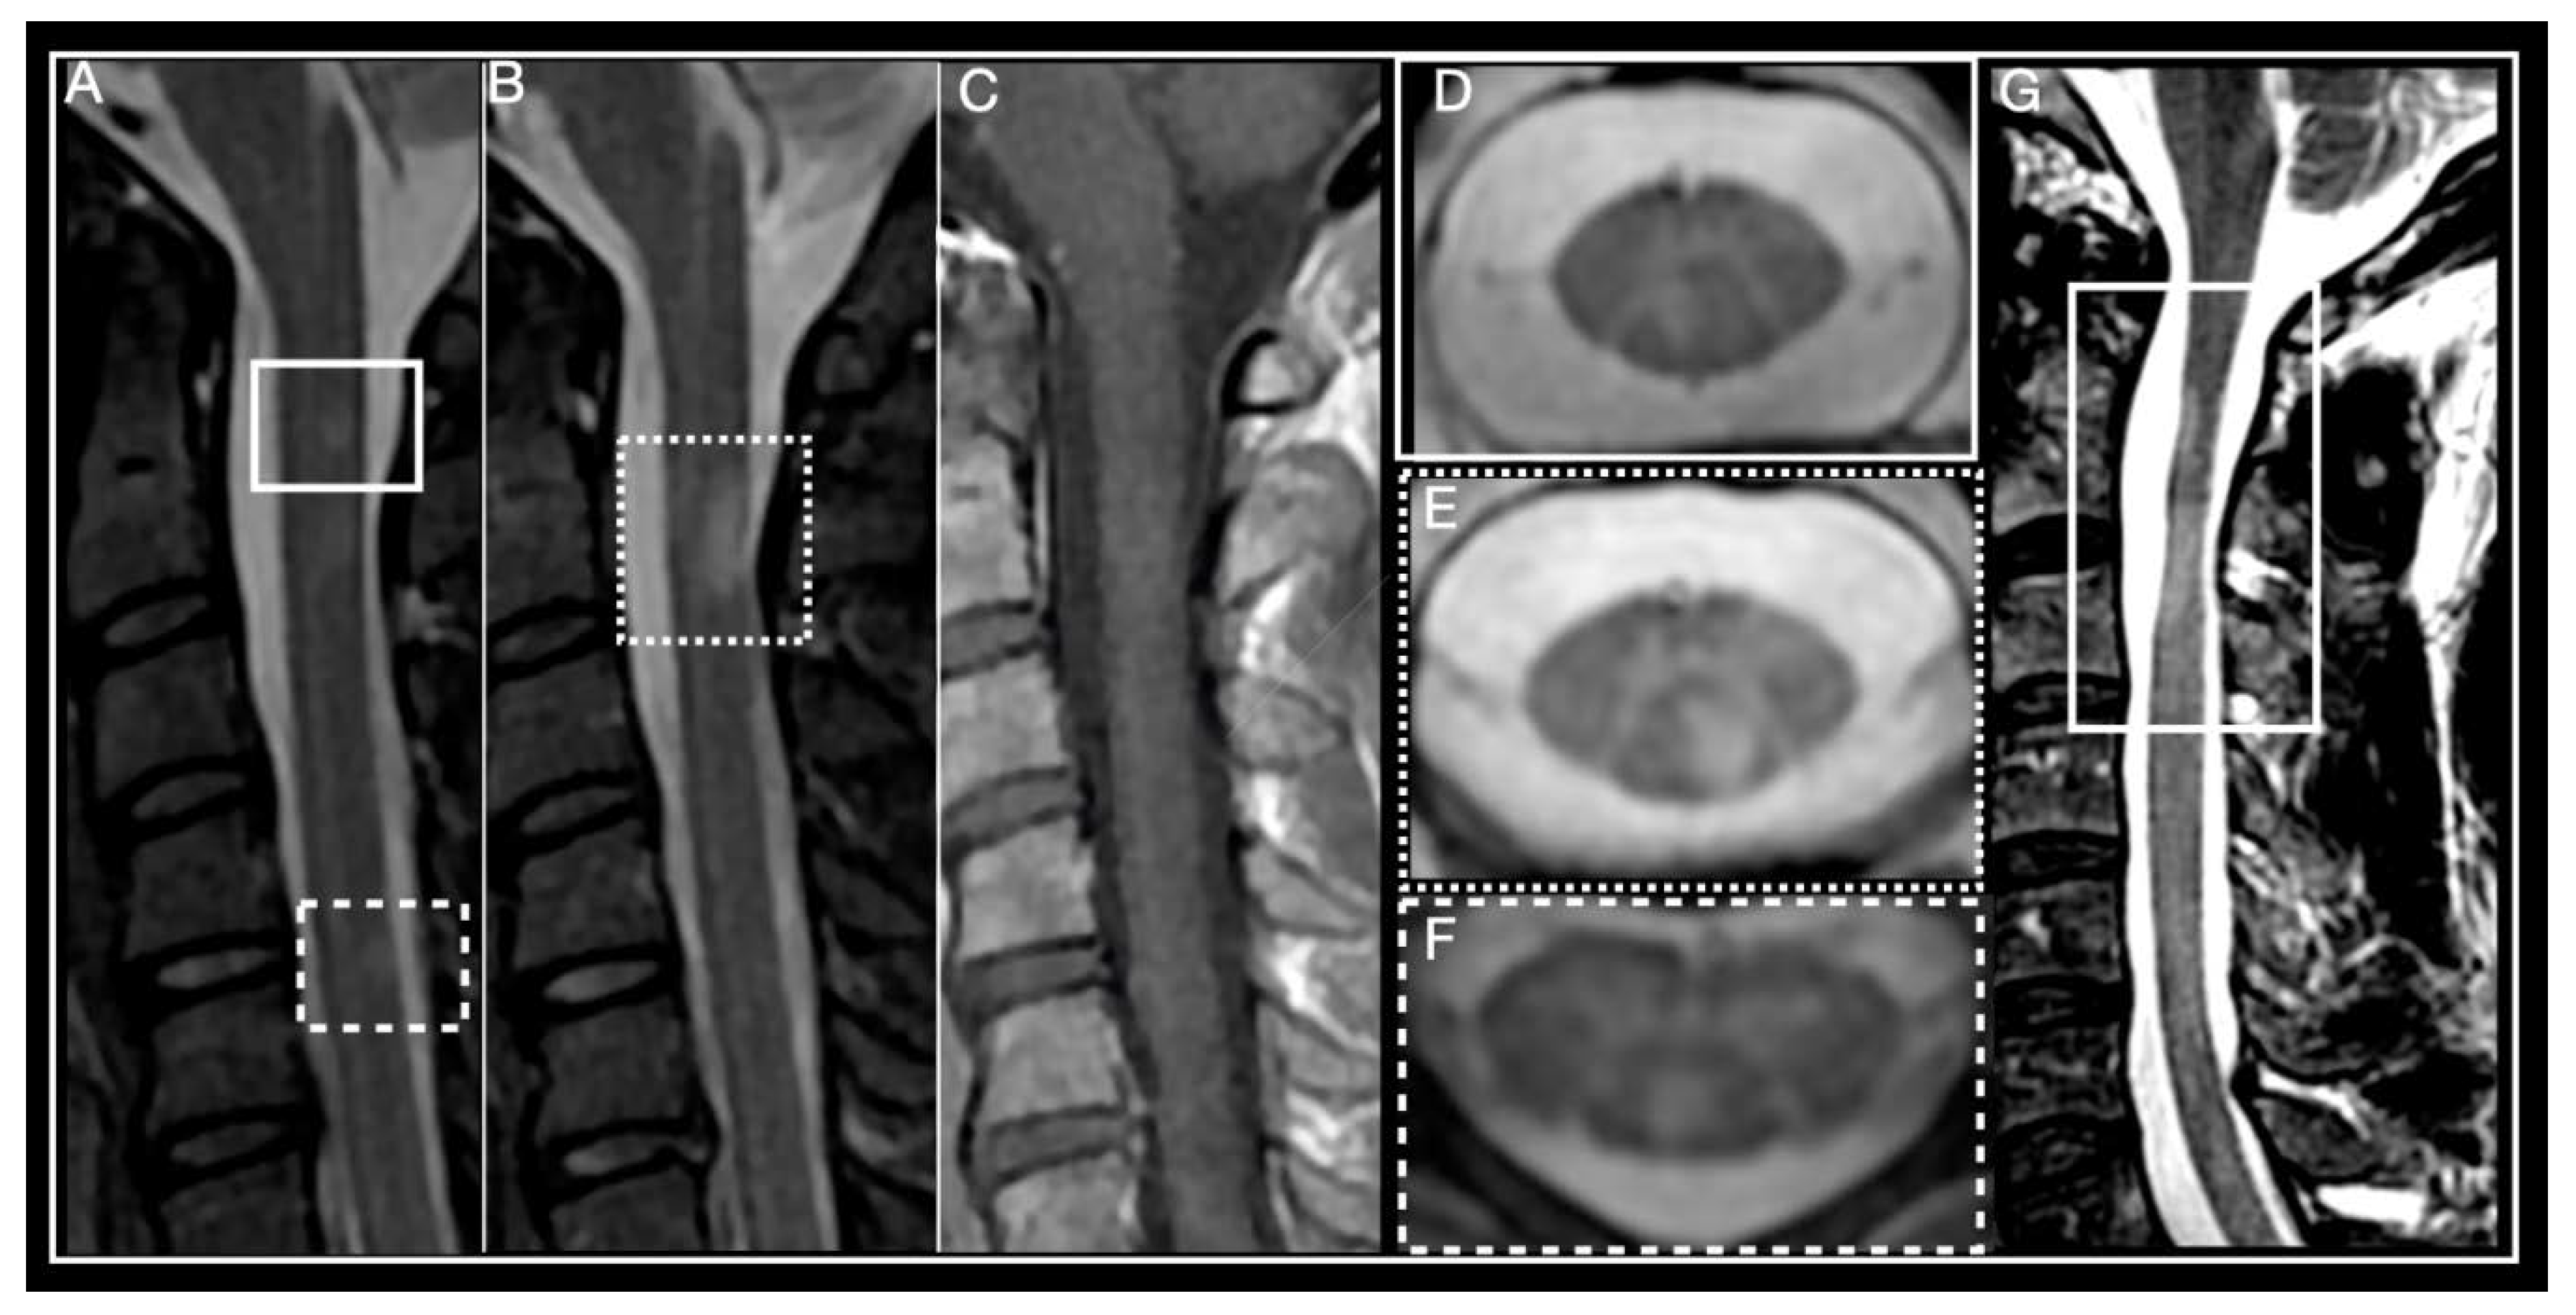

Figure 1.

Multiple Sclerosis myelitis. (A–F) 32-year-old woman diagnosed with relapsing remitting course (RRMS) 2 years earlier, EDSS 0. (A,B) Sagittal short-tau inversion recovery (STIR) showing small, focal, chronic, peripheral lesions. (C) Sagittal post-contrast T1 weighted, absence of enhancement, T2 lesions are isointense. (D–F) axial T2 multiple-echo recombined gradient echo (MERGE). (D) right paramedian posterior lesion corresponds to lesion framed by a box in (A). (E) left paramedian posterior lesion corresponds to lesion framed by a dotted box in (A). (F) posterior lesion corresponds to lesion framed by a dotted line in (A). (G) 46-year-old man diagnosed with primary progressive multiple sclerosis (PPMS) in 2011, EDSS 6. Sagittal T2-weighted, framed area shows multiple sclerosis (MS) lesions and spinal cord atrophy.

Often more than one demyelinating plaque is present in spinal cord MRIs from patients with MS. The cervical spine (53–59%) is the most common location, followed by the thoracic region (20–47%) [10]. Lesions usually present as hyperintense on T2-weighted and isointense on T1-weighted sequences. Gadolinium enhancement is variable and depends mainly on acquisition timing, with acute lesions usually enhancing during 4–8 weeks [29,30]. Most MS lesions are small in size, wedge-shaped in axial and ovoid-shaped in sagittal views, and predominantly found in ascending sensory (i.e., posterior column), and descending motor (i.e., corticospinal) spinal cord tracts, because of the high myelin concentration within these fascicules [31]. Rarely, they may extend to involve central grey matter, occupying over half the cross-sectional area of the cord. Small focal lesions may coalesce to form more extensive ones, involving three or more segments, particularly in cases of progressive MS. High-resolution axial MRI demonstrates these images actually result from the confluence of multiple discrete lesions [25,32].

Spinal cord atrophy (Figure 1G) present in early stages of the disease may correlate with degree of disability and predict long term outcome [38,40]. Measuring changes in cross-sectional area at the cervical level yields the most reproducible results and shows closest correlation to clinical findings [41,42]. Grey matter atrophy on the other hand correlates more strongly with degree of physical disability than other MRI parameters of brain and cord atrophy [43,44,45]. Notably, a significant association between reduced cervical cord sectional diameter and disability progression has been demonstrated in different studies, independent of brain atrophy [46,47,48]. Cord atrophy has also been associated with reduction in retinal nerve layer thickness [48], suggesting it is probably part of a global pathological process and not just determined by local damage.